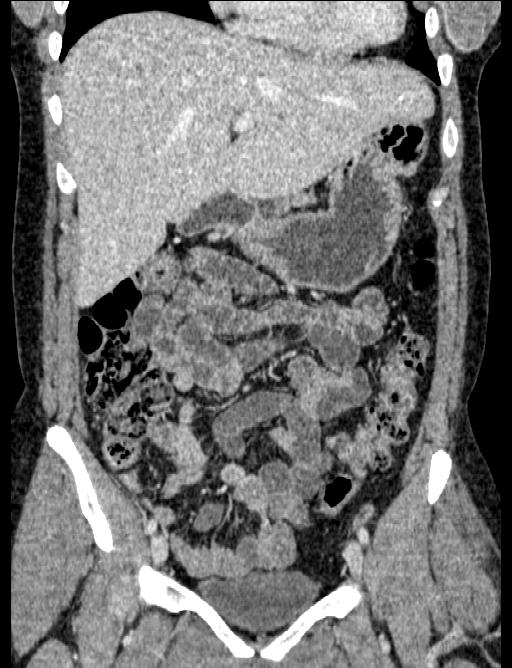

2010